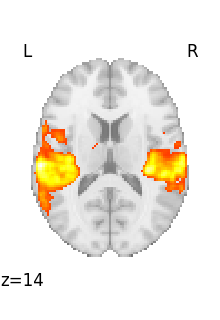

Looping through selected volumes in a 4D file¶

If we want to plot selected volumes in this 4D file, we can use index_img with the slice constructor to select the desired volumes.

Afterwards, we’ll use iter_img to loop through them following the same formula as before.

selected_volumes = image.index_img(rsn, slice(3, 5))

If you’re new to Python, one thing to note is that the slice constructor uses 0-based indexing. You can confirm this by matching these slices to the previous plot above.